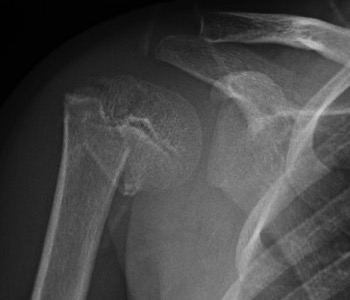

Case: 16 year old boy

Initial injury 18 months post injury